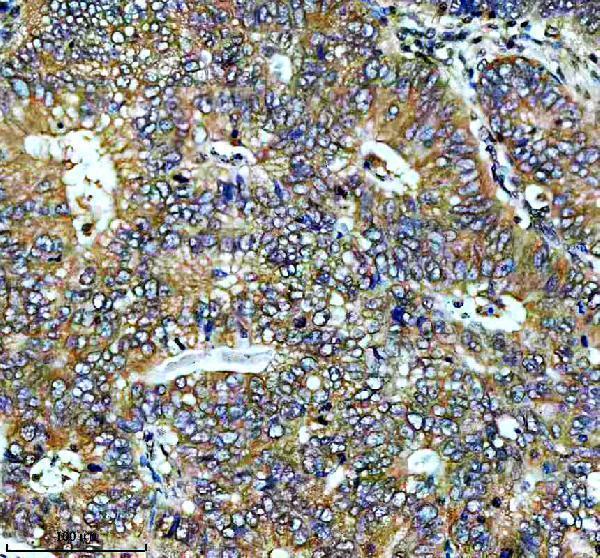

Facts about Dual specificity mitogen-activated protein kinase kinase 2.

| Gene Name: | MAP2K2 |

Cytoplasm. Membrane; Peripheral membrane protein. Membrane localization is probably regulated by its interaction with KSR1.